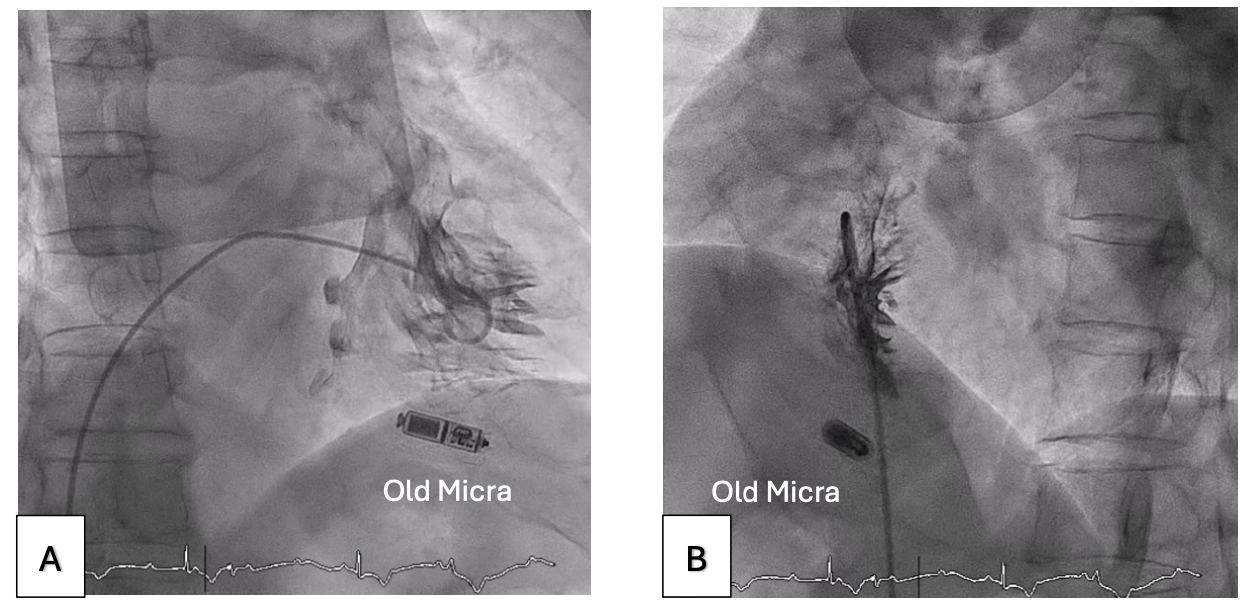

Right ventriculography was performed via right femoral venous access to outline the right ventricular (RV) septum (Figure 1, Video 1). A 5F Arrow temporary venous pacing (TVP) catheter (Teleflex) was then used to measure the pacing thresholds at multiple sites along the RV septum. The site with the lowest threshold was identified and fluoroscopically roadmapped in right and left anterior oblique (LAO) views to guide deployment (Figure 2, Video 2). The venous sheath was exchanged for the 23F Micra delivery sheath, and the new Micra AV was successfully deployed at the pre-identified site (Figure 3, Video 3), achieving a pacing threshold of 0.5V at 0.24 milliseconds and an estimated battery longevity of greater than 10 years.